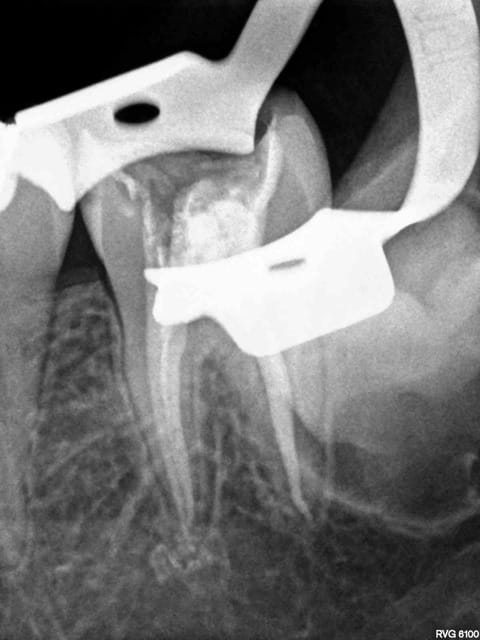

C'est quoi la proba d'avoir une deuxième bio à 5 canaux en 2 semaines?

(la radio excentrée est dégueulasse, mais ça montre les doubles courbures, quelques peu minimisées par l'angulateur...